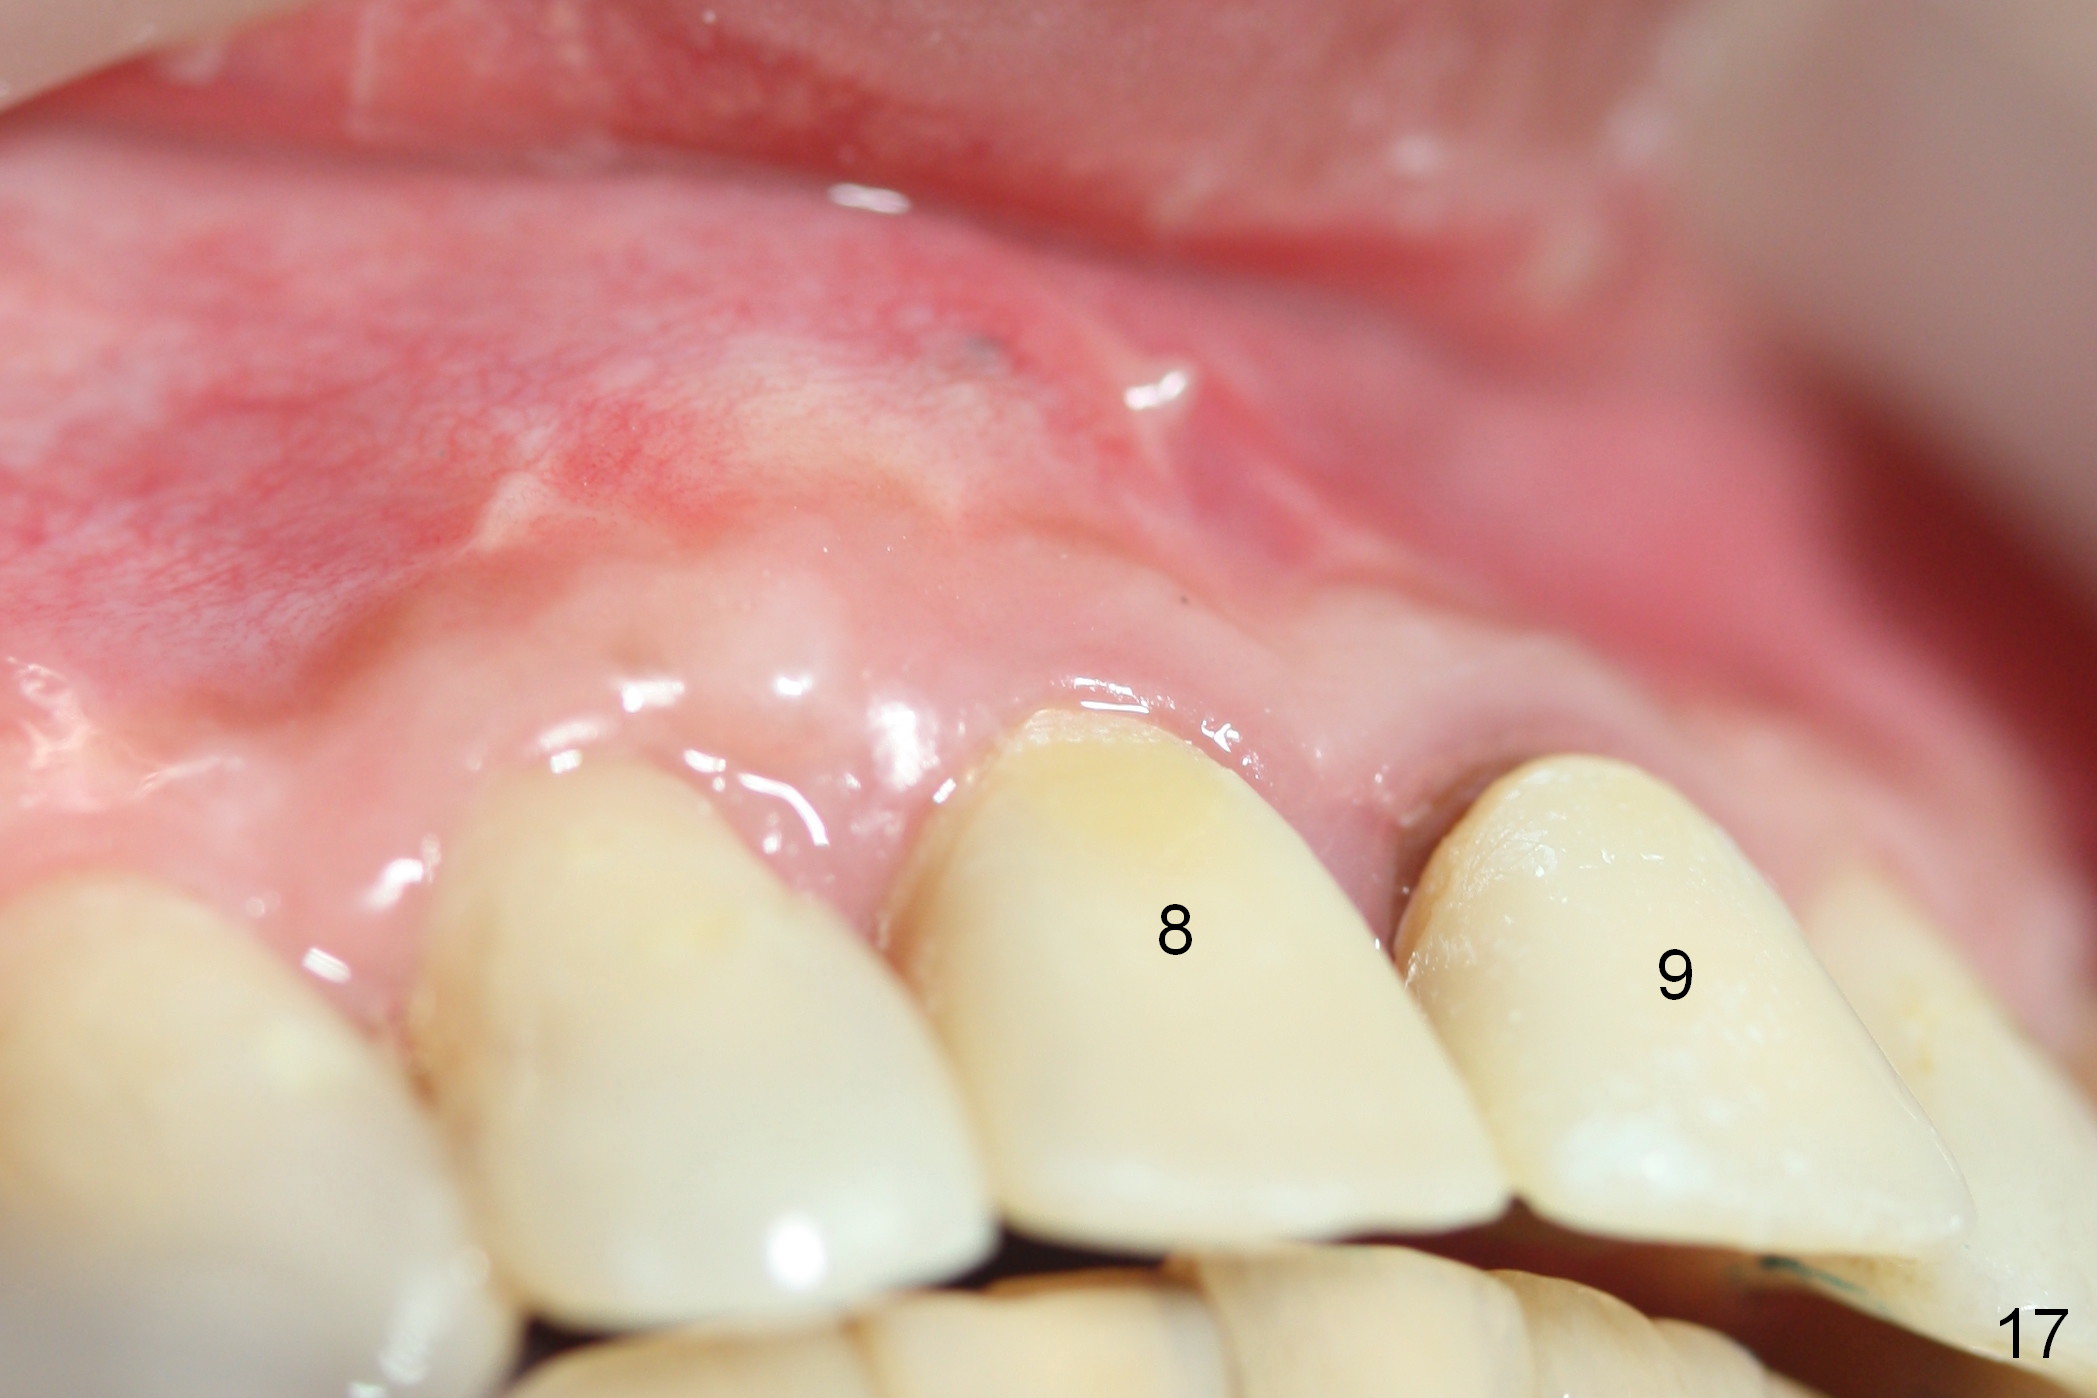

Nine months postop, the gingival margin is symmetrical over the provisional crowns at #8 and 9 (Fig.16).  There is no bulging or concavity associated with the implant at #8 (Fig.17).  Screw (Fig.16 <) removal is scheduled prior to final restoration.  The gingiva is healthy 1 year 7 months post cementation (Fig.18).